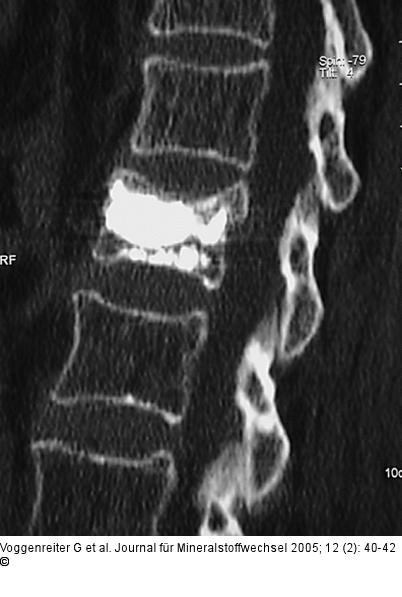

Abbildung 4a-d: Wirbelkörperaufrichtung - postoperative Darstellung Postoperative Darstellung der Zementverteilung und der Wirbelkörperaufrichtung im CT. Trotz Beteiligung der Wirbelkörperhinterkante kam es zu keiner weiteren Einengung des Spinalkanals, sondern durch Ligamentotaxis eher zu einer Erweiterung. Das postoperative Kontroll-CT zeigt eine Reduktion der Kyphose bei klinischer Beschwerdefreiheit der Patientin. |

Postoperative Darstellung der Zementverteilung und der Wirbelkörperaufrichtung im CT. Trotz Beteiligung der Wirbelkörperhinterkante kam es zu keiner weiteren Einengung des Spinalkanals, sondern durch Ligamentotaxis eher zu einer Erweiterung. Das postoperative Kontroll-CT zeigt eine Reduktion der Kyphose bei klinischer Beschwerdefreiheit der Patientin. |